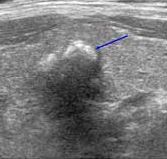

갑상샘 석회화란?석회는 조직과 세포로 칼슘이 비정상적으로 증식한 것으로, 초음파 검사로 흰색 점, 선과 응집된 형태 등으로 나타납니다.갑상샘 석회화는 초음파 검사로 분포의 정도, 모양, 크기, 위치 등을 통해서 양성인지 악성인지 진단합니다.양성 석회화는 표면이 분명하고 규칙적인데 악성 석회화는 거대 석회화의 경우나, 흰 점이 있었으며 크기가 매우 작은 소견이 보이지만 미세 석회화의 경우 깨끗이 제거하는 것이 어려운 재발 가능성이 높습니다.

▶ 좌) 불균일한 결절 내부에 미세석회화를 여러 개 볼 수 있는 악성결절, 우측) 2mm 이상의 거대석회화를 볼 수 있는 악성결절(출처: 서울대암병원)